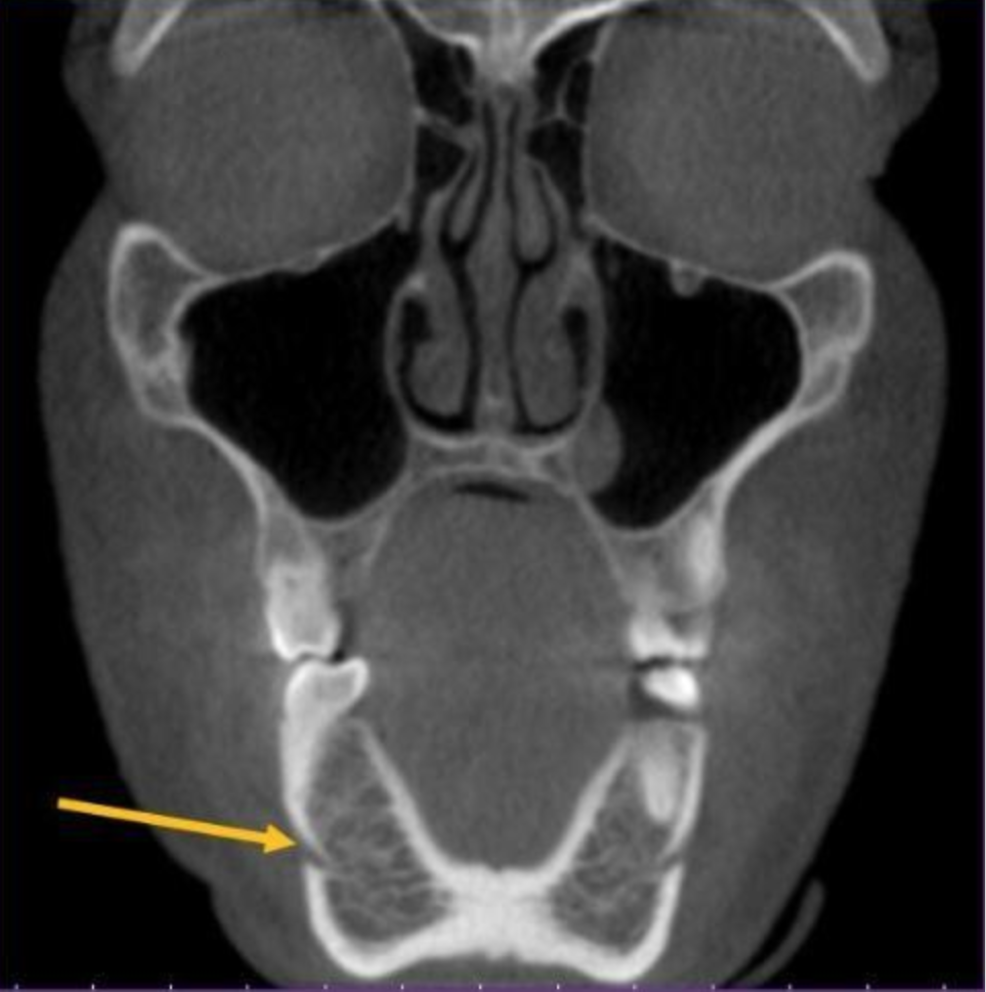

mental foramen

what is the structure indicated by the arrow